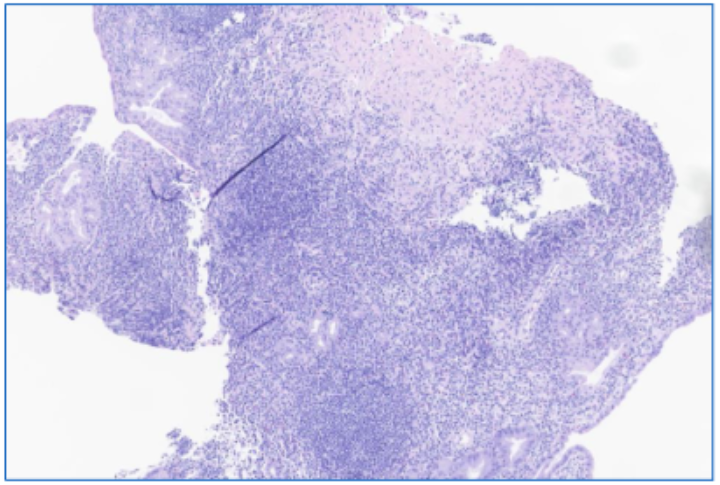

腹泻3年+小肠溃疡+黏膜萎缩,大剂量泼尼松治疗无效,这种极易漏诊的罕见病如何破局?

病史摘要:63岁男性患者,有3年慢性腹泻史,近期加重,每日排便4 - 8次,伴体重减轻5kg。诊疗过程:查体见消瘦、肠鸣音亢进,BMI 16.4kg/m²。实验室检查有多项异常,腹部CT见腹膜后血管迁曲及肠系膜淋巴结肿大,结肠镜示右半结肠炎,PET - CT示结肠炎症和轻度高代谢淋巴结,小肠镜见多发溃疡等。排除乳糜泻等疾病,血清蛋白电泳提示M蛋白水平升高。初始经验性治疗效果不佳